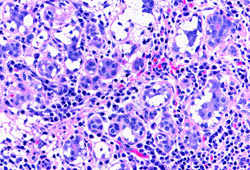

In idiopathic granulomatous mastitis, non-necrotising granulomatous inflammation is centred on lobules that clinically may result in a painless mass. [Figure caption and citation for the preceding image starts]: Microscopy image of non-necrotising granulomatous inflammation in the breastFrom the collection of Liron Pantanowitz, MD, Tufts University School of Medicine, MA [Citation ends].